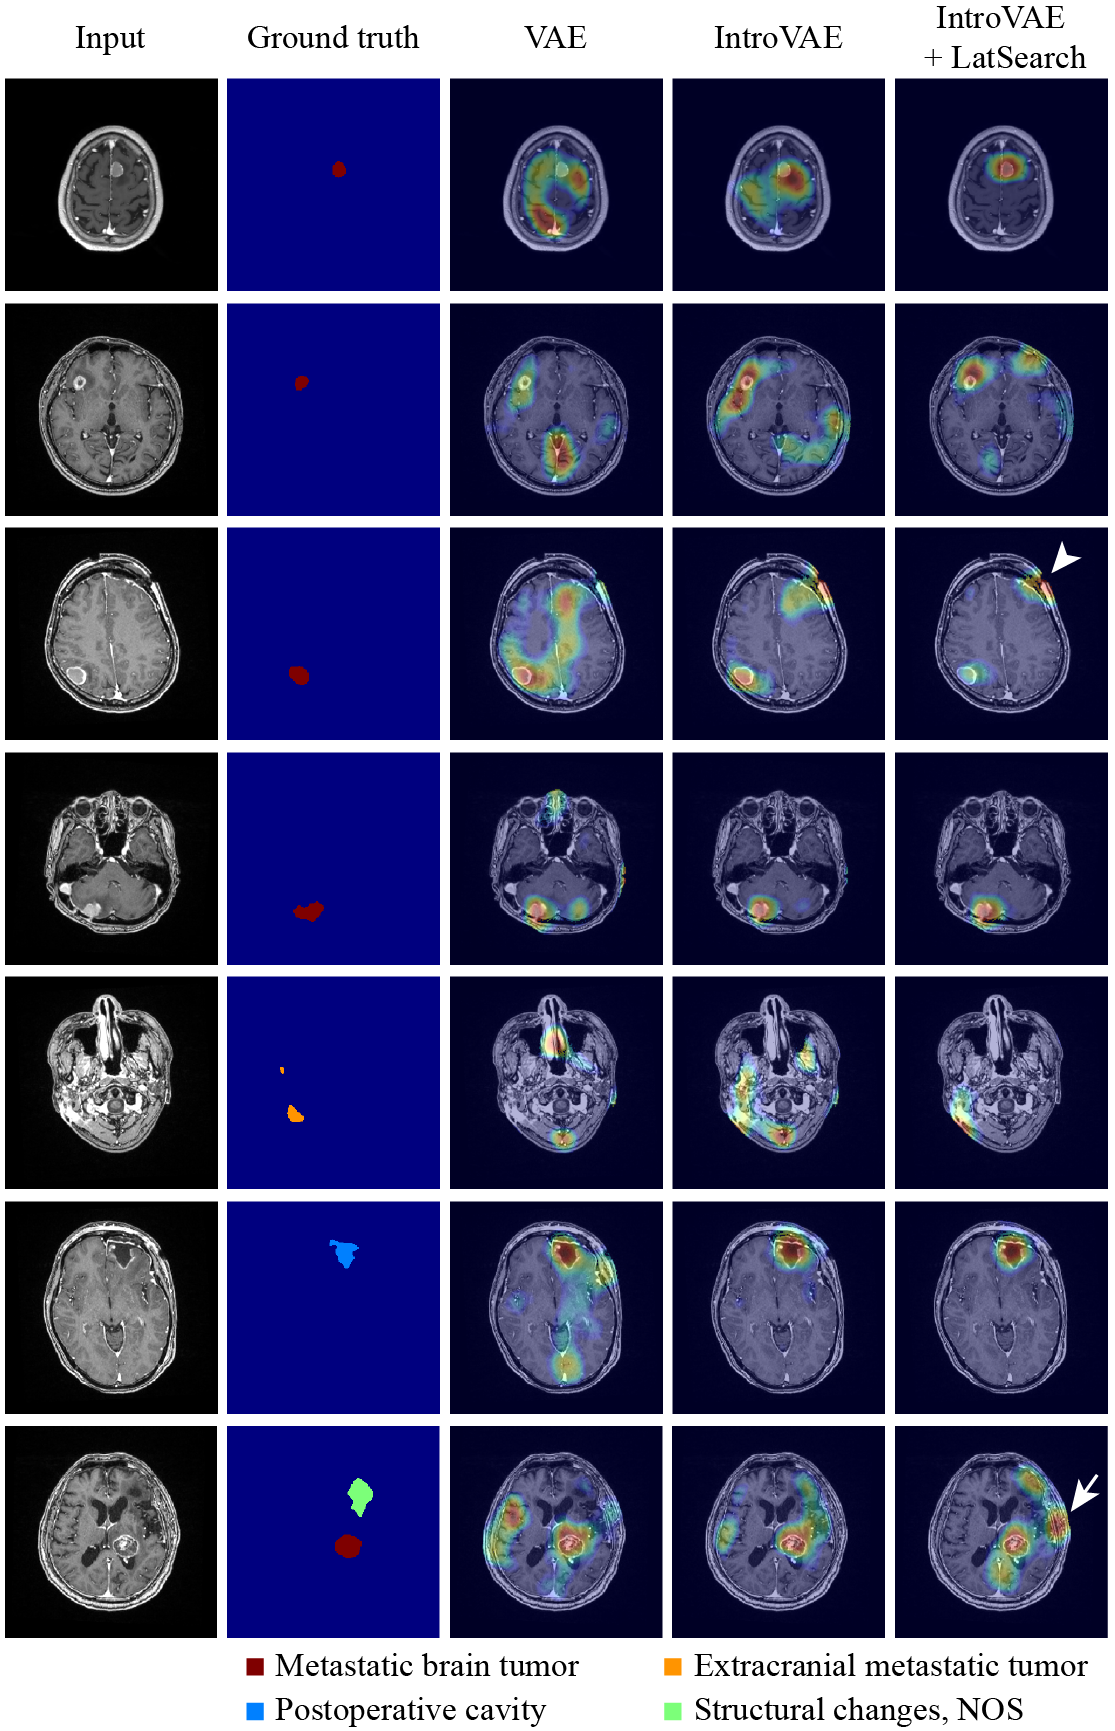

Finally, the visual examples are shown in Fig. 7. When using IntroVAE+LatSearch, metastatic brain tumors, extracranial metastatic tumors, and postoperative cavities were associated with distinct abnormality scores co-localized in the labeled regions. In contrast, other structural changes yielded accumulations of abnormality scores in the labeled region; however, the distribution was not consistent. It is noteworthy that some undefinable structural deformations outside the brain parenchyma were detected based on the intensity of the score, as indicated by the arrow and arrowhead.